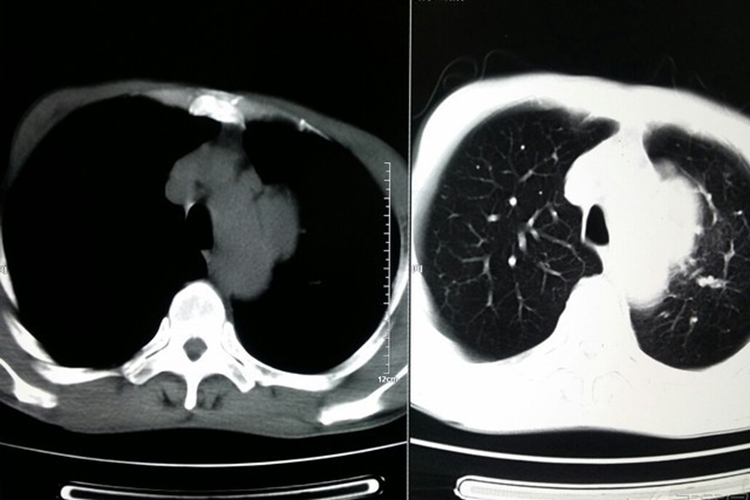

肺癌又称原发性支气管肺癌,临床常见咳嗽、血痰、胸痛、发热、气促等症状。影像学表现可分为中央型肺癌和周围型肺癌两种,具体如下:

中央型肺癌:发生在肺段和段以上支气管,表现为病变处支气管壁增厚、支气管腔狭窄;肺门出现形态不规则的软组织肿块;远端肺组织阻塞性改变,包括阻塞性肺炎、肺不张,表现为远端肺组织实变,或肺叶、肺段均匀性密度增高,伴肺纹理聚拢、体积缩小或右肺上叶不张时,下缘形成反“S”征。

周围型肺癌:发生在肺段以下支气管,表现为肺内结节或肿块;病灶形态不规则,呈分叶状(分叶征);边缘多发细短毛刺(毛刺征);偏心性空洞,或伴有壁结节;相邻胸膜凹陷,伴线形、喇叭口样索条影牵拉改变;增强扫描呈轻、中度不均匀强化。